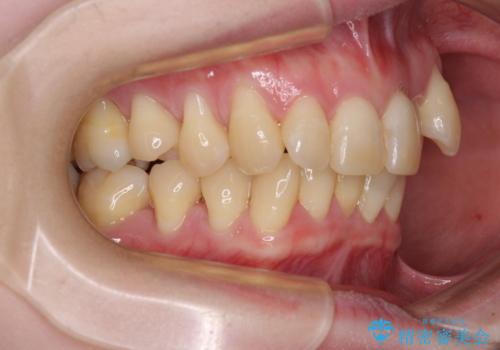

八重歯と先天欠損の歯列 ワイヤー矯正ですっきりと

- 八重歯と正中のズレを気にして来院された患者様です。

上顎左側が八重歯になっており、上顎正中が左側にずれていました。

上顎左側の第一小臼歯を抜歯し、補助装置を用いて正中位置を改善しながら八重歯を解消していくこととしました。

下顎前歯が1本欠損していたため、上下正中の位置が合わせるという目標はなく、鼻筋に上顎正中を合わせていくように移動を行いました。